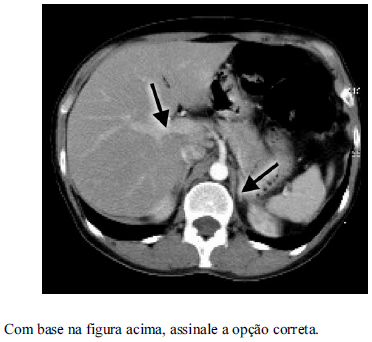

A imagem mostra um estudo com contraste, na fase portal.

A glândula adrenal esquerda está assinalada pela seta preta maior.

A veia cava inferior está assinalada pela seta preta menor.

Entre as indicações do estudo dinâmico com contraste do abdome superior, destaca-se a caracterização dos nódulos adrenais.